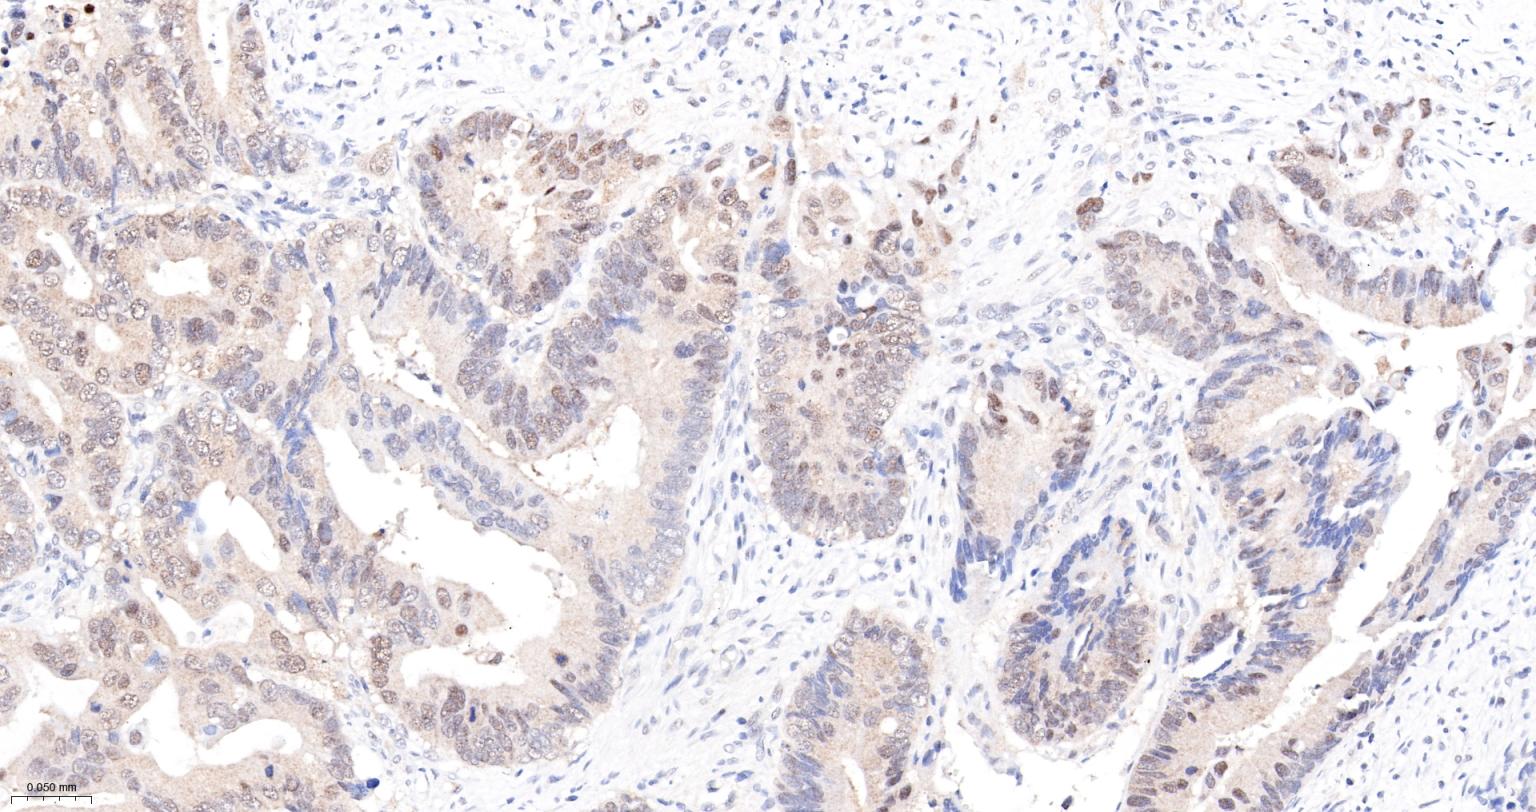

Paraformaldehyde-fixed, paraffin embedded Human Gastric Cancer; Antigen retrieval by boiling in sodium citrate buffer (pH6.0) for 15 min; The section was incubated with CK II alpha Monoclonal Antibody, Unconjugated (bsm-61133R) at 1:200 overnight at 4°C, followed by conjugation to the bs-0295G-HRP and DAB (C-0010) staining.

Paraformaldehyde-fixed, paraffin embedded Human Breast Cancer; Antigen retrieval by boiling in sodium citrate buffer (pH6.0) for 15 min; The section was incubated with CK II alpha Monoclonal Antibody, Unconjugated (bsm-61133R) at 1:200 overnight at 4°C, followed by conjugation to the bs-0295G-HRP and DAB (C-0010) staining.

Paraformaldehyde-fixed, paraffin embedded Human Colon Cancer; Antigen retrieval by boiling in sodium citrate buffer (pH6.0) for 15 min; The section was incubated with CK II alpha Monoclonal Antibody, Unconjugated (bsm-61133R) at 1:200 overnight at 4°C, followed by conjugation to the bs-0295G-HRP and DAB (C-0010) staining.